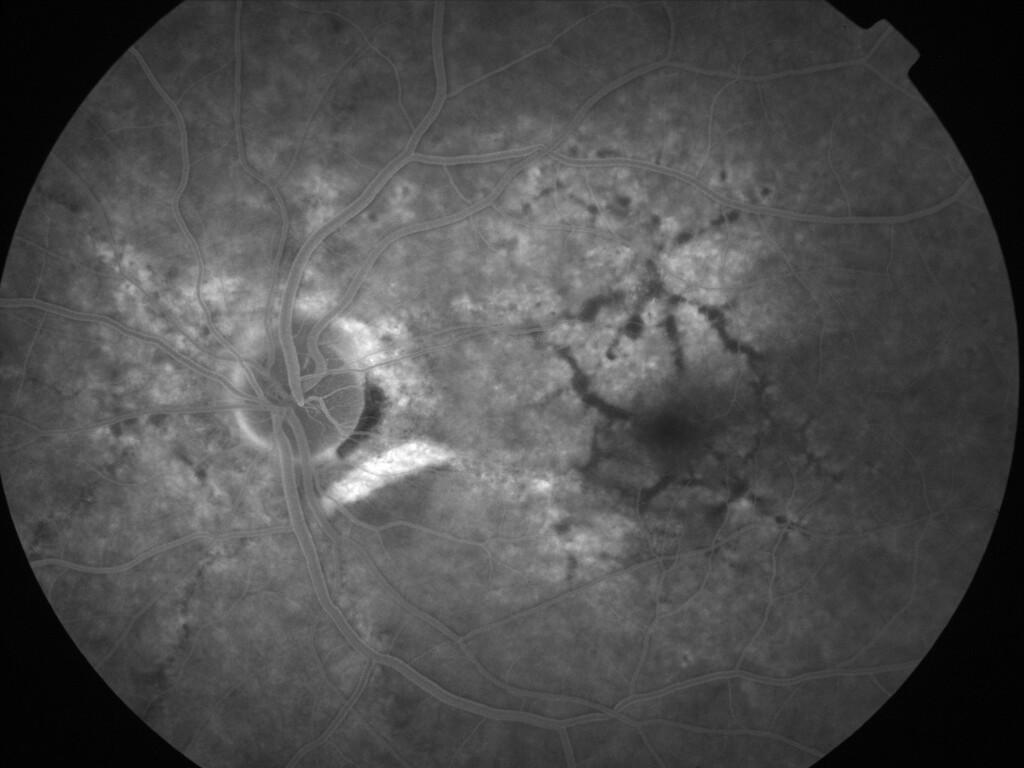

IMG0037.jpg